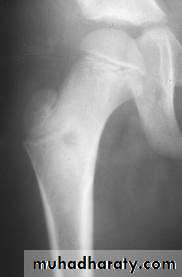

Plain x-ray

Show local sclerotic thickening of the shaft that may obscure the small central nidus within the area of rarefaction.The nidus is best seen on a fine cut CT scan

Intense uptake on an isotope bone scan.

Imaging13

C T scan